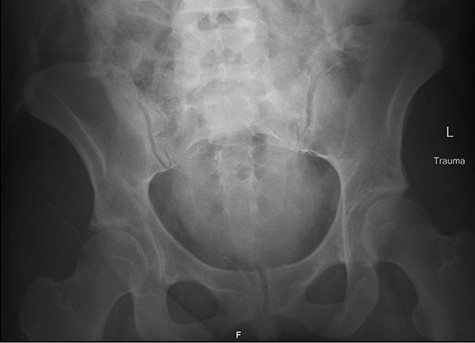

Ureteral injuries are commonly missed in trauma. Possible reasons for this include prioritization of severe injuries, hemodynamic instability preventing radiographic imaging or low clinical concern due to misperception that the retroperitoneal location of ureters is completely protective [1,2]. Usually, injuries are associated with traumatic pelvic fractures or penetrating injuries and are limited to one ureter; however, we present a case where the patient experienced complete, bilateral ureteral injury without any associated pelvic fracture.

Fetal HR was measured at 135 bpm. Chest X-ray revealed a small apical pneumothorax and a fractured right clavicle. She was taken to the computed tomography (CT) scanner where CT-CAP with contrast revealed a Grade 2 liver laceration, Grade 3 splenic laceration and bilateral Grade 4 kidney injuries with extravasation of contrast on the renal delay, suggestive of urine extravasation. No pelvic fracture was found on imaging (Figs 1 and 2).